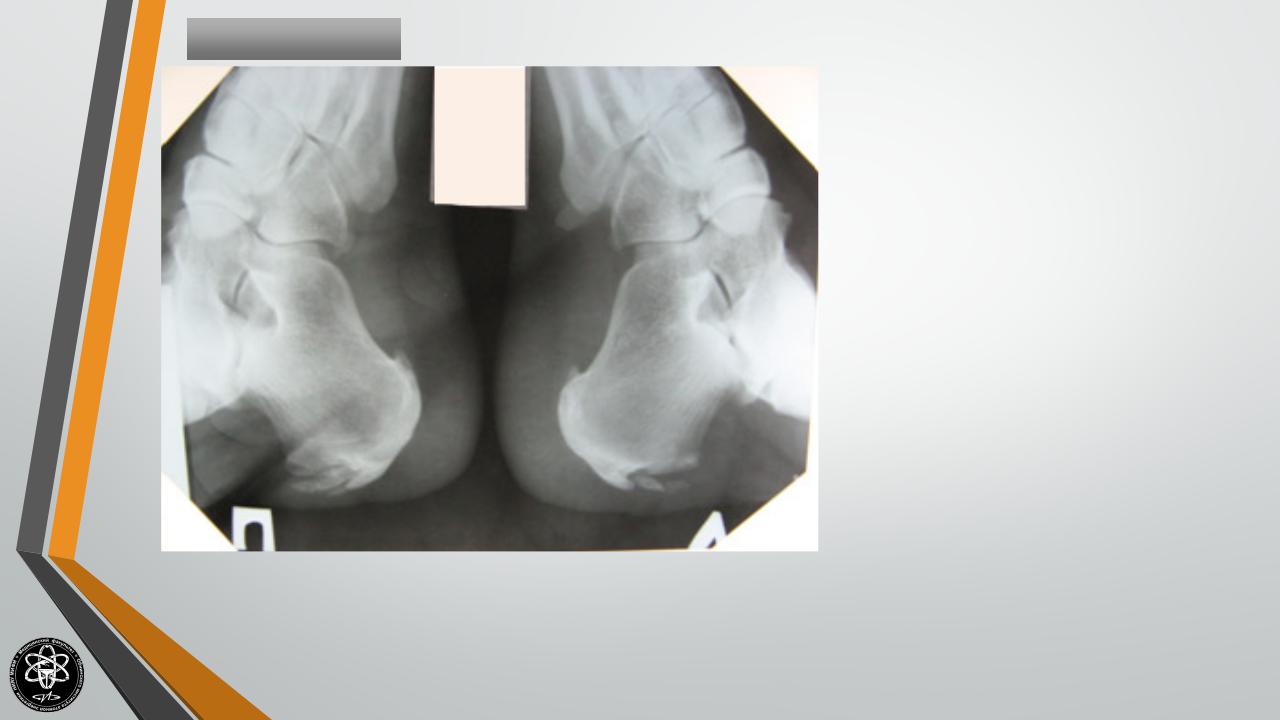

Болезнь Шинца |

Остеохондропатия |

бугра |

пяточной кости. Как правило, |

поражает детей в возрасте 7-14 |

лет. |

Сопровождается |

появлением |

болей |

и |

припухлости. |

Лечение остеохондропатии амбулаторное, включает в себя ограничение нагрузки, электрофорез с кальцием и тепловые процедуры.